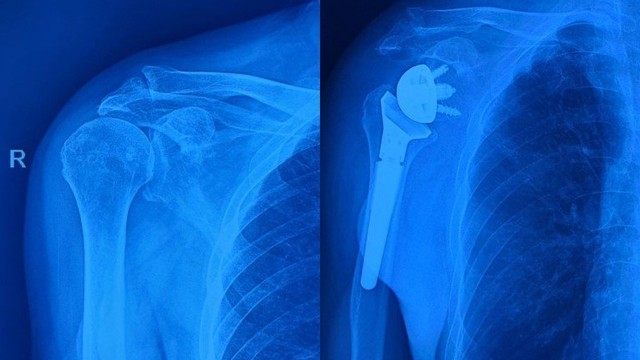

Khớp vai là một khớp cầu nằm ở vùng vai, đóng vai trò quan trọng trong việc giúp cánh tay có thể di chuyển linh hoạt. Do tính chất phức tạp và linh hoạt của khớp vai, dễ bị tổn thương và đau đớn. Vậy những tổn thương nào cần phải thực hiện phẫu thuật thay khớp vai và thay khớp vai là gì hãy cùng tìm hiểu qua bài viết dưới đây.